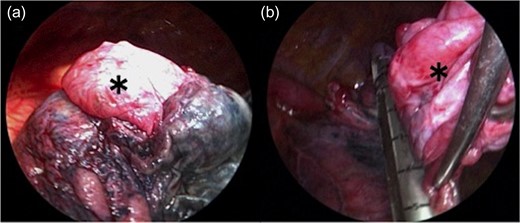

Left lower lobectomy and lymph node dissection were performed. Preoperative computed tomography imaging revealed multiple bullae in the apex of the left lung and very thin bullae walls (Fig. 2A). Concerned that the patient would develop a second primary lung cancer or pneumothorax in the future, we simultaneously performed a bullectomy for two bullae with a lobectomy (Fig. 2B). Because the patient’s lung was highly emphysematous, linear staplers with PGA felt (Endo GIA™ Reinforced Reload with Tri-Staple™ Technology, cartridge color: purple, MEDTRONIC, Tokyo, Japan) were used for the bullectomy. We confirmed the absence of bleeding in the thoracic cavity and completed the operation (Video 1). The drainage from the thoracic tube turned bloody beginning 1 h after the operation. The drainage volume increased, and 600 ml of bodily drainage was observed for 2 h after the drainage had turned bloody. A chest X-ray imaging examination was performed, which confirmed fluid accumulation in the left thoracic cavity (Fig. 3). Because the patient’s anemia had also progressed, as compared with preoperative measurements (preoperative hemoglobin, 12.8 g/dl; 3-h postoperative hemoglobin, 9.1 g/dl), we determined that sustained bleeding had occurred in the thoracic cavity; we subsequently decided to carry out a reoperation to perform hemostasis. No air leakage was observed during the period between both operations.

The bulla (*) wall in the apex of the lung was very thin (a). Following left lower lobectomy, the resection of emphysematous bullae (*) was performed (b).